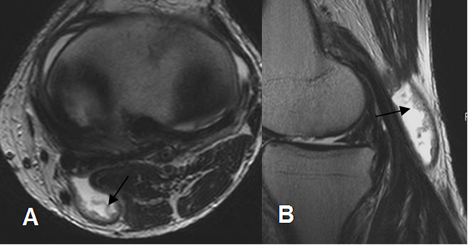

Fig 176. Quiste de Baker.

A: RM axial en T2 y B: RM axial en FFE. Lesión quística entre los músculos gemelo interno (Flecha gruesa) y semimembranoso (Flecha delgada), que corresponde a quiste de Baker.